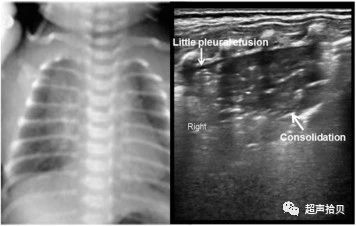

2.肺实变:(图2,图3,图4)

图2:新生儿肺部超声检查在胎儿(胎龄37周;剖宫产分娩;出生体重3,700克)在分娩后29小时,无胎儿窒息。 婴儿出现呼吸窘迫,发热,白细胞计数为30×109 / L,中性粒细胞为81%,血小板计数为67×109 / L,C反应蛋白水平为39 mg / L。 肺部超声检查显示肺部不规则的肺实变区,右肺大部分有空气支气管征,胸膜线和A线消失,少量胸腔积液,肺部滑动消失,肺部脉搏减少。 胸部影像学证实了肺炎的诊断,这在右侧更为严重。